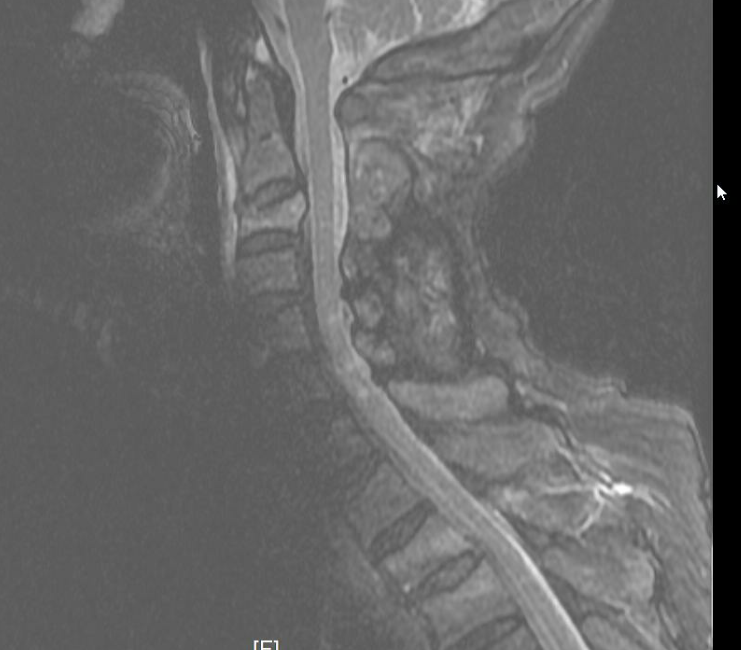

▲颈部带金属的膏药贴导致的伪影